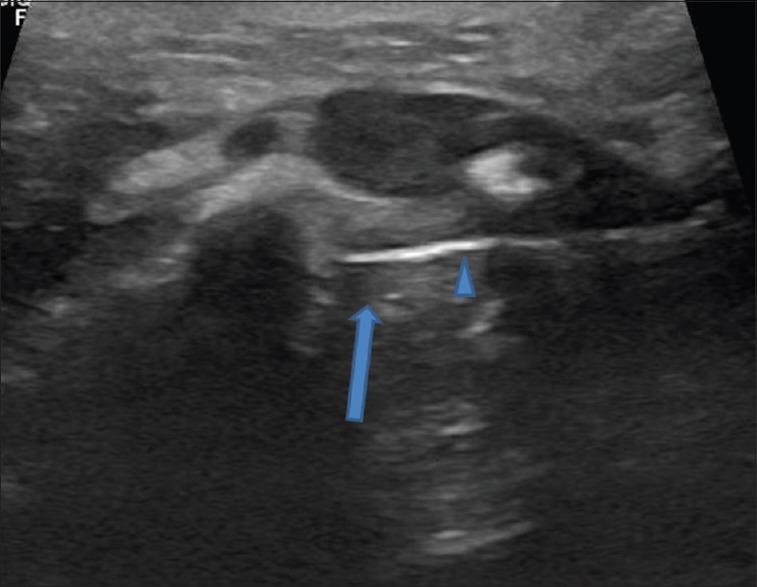

Metastasis to the thyroid gland is rare; furthermore, intrathyroid metastasis from head and neck squamous cell carcinoma (SCC) is very unusual, with only nine previously documented cases four from intrathyroid metastasis from nasopharyngeal carcinoma, two from oral cavity, one each from oropharynx, larynx, and parotid. The reported case series are unique in nature and illustrates the role of fluorodeoxyglucose positron emission tomography-computed tomography (PET-CT) and ultrasound-guided biopsy in diagnosing clinically occult isolated intrathyroidal metastasis, which helps in the best management for an isolated intrathyroid metastases. This study details the cases of three patients who were diagnosed with intrathyroidal metastasis from SCC of the tongue by PET-CT, followed by USG-guided biopsy, who were treated with either surgery and or chemotherapy. Although intrathyroidal metastasis is an uncommon occurrence and signifies poor prognosis, early detection of an isolated intrathyroidal metastasis on imaging in an appropriately selected patients, radical surgery, and/or chemotherapy improve local control and quality of patient's life.

甲状腺转移瘤较为罕见;此外,头颈部鳞状细胞癌(SCC)发生甲状腺内转移的情况非常少见,此前仅有9例记录在案的病例——4例来自鼻咽癌的甲状腺内转移,2例来自口腔,1例分别来自口咽、喉和腮腺。所报道的病例系列具有独特性,说明了氟脱氧葡萄糖正电子发射断层扫描-计算机断层扫描(PET-CT)和超声引导下活检在诊断临床隐匿性孤立性甲状腺内转移瘤中的作用,这有助于对孤立性甲状腺内转移瘤进行最佳管理。本研究详细介绍了3例经PET-CT诊断为舌部SCC甲状腺内转移、随后接受超声引导下活检、并接受手术和/或化疗的患者病例。虽然甲状腺内转移并不常见且预示预后不良,但在适当选择的患者中通过影像学早期发现孤立性甲状腺内转移瘤、进行根治性手术和/或化疗可改善局部控制并提高患者生活质量。